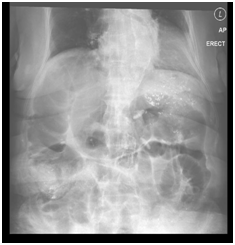

A 76year old Chinese female with multiple co-morbidities was admitted after a fall while sustaining a stable head injury. Her past medical history includes hypertension, dyslipidemia, ischemic heart disease with a history of angioplasty and ejection fraction of 30% and moderate mitral regurgitation, end-stage renal failure on hemodialysis, gout, asthma, previous sigmoid cancer with left hemicolectomy 2years ago and recurrent falls. After a few days of observation in the hospital, while waiting to be discharged from hospital to a step-down care at community hospital after, she suddenly presented with right sided abdominal pain. The pain was associated with two episodes of non-bloody, non-bilious vomiting and abdominal distension. Upon physical examination, she was hypotensive, with cold clammy extremities. Her abdomen was mildly distended, with generalized tenderness and guarding especially over the right side. The laboratory investigation shows a high white blood count of 16.95 with normochromic and normocytic anemia, as well as a raised lactate level of 3.5 and metabolic acidosis on the arterial blood gas panel (pH 7.36 pCO2 37.8 pO2 37.8 pO2 183.8 Base Excess -4.3 Bicarbonate 20.9). C-Reactive protein (CRP) level was 333. Acute intestinal obstruction was suspected and a supine abdominal X-ray (AXR) was done immediately which showed multiple gas-filled prominent loops of bowel (Figure 1).

Figure 1 AXR showing dilated bowels.